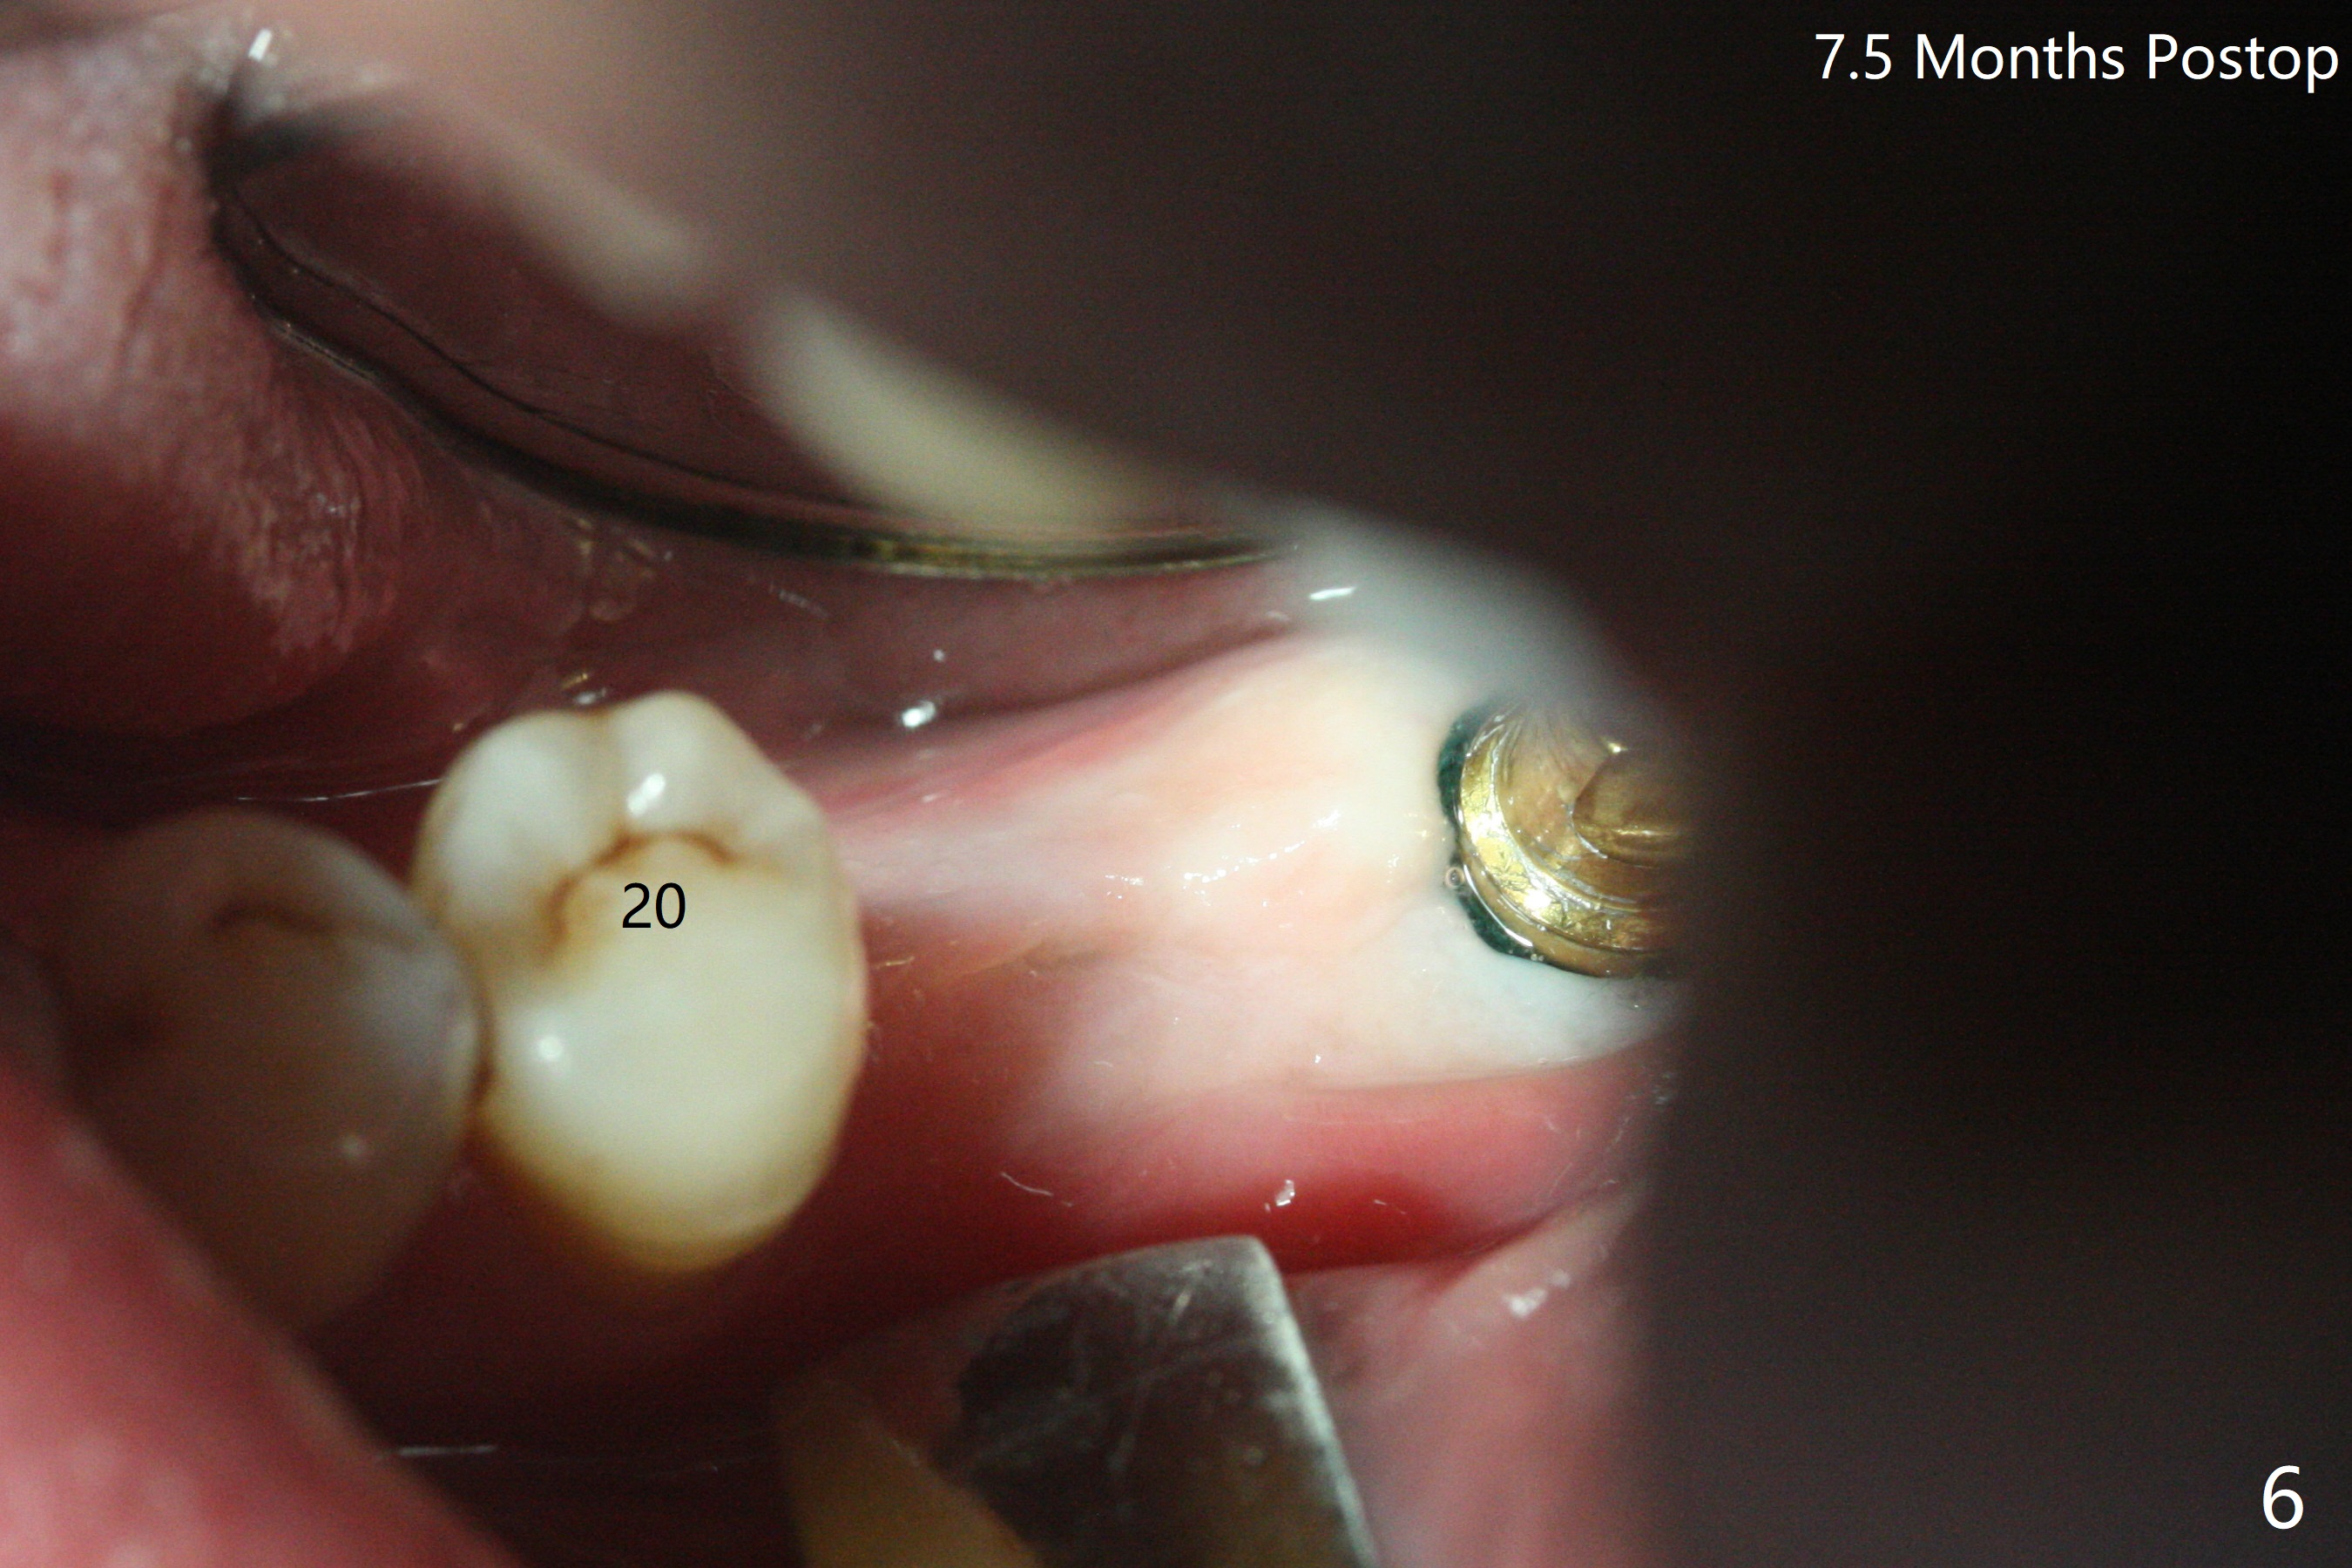

After finishing osteotomy with guide, a 5x14 mm tissue-level implant tap is used without guide because of limited mouth opening. It is not parallel to the implant at #19 (Fig.1). A bone-level implant is barely able to be placed with guide; it is parallel to #19 implant (Fig.2). Pre- and intra-op exam confirms periimplantitis at #19. In addition the horizontally impacted #17 has caries. A large incision is made for #19 debridement and bone graft. #18 bone graft (Fig.2 *) and #17 extraction and Osteogen plug (O) placement. Postop CT shows poor trajectory of #19 implant (Fig.3 (coronal section) free hand placement), which is associated with screw loosening and periimplantitis (lingual (L) threads supracrestal). In contrast #18 implant has good trajectory and placement level (Fig.4). The mesial defect of #19 seems to have been repaired and the implant at #18 osteointegrates 7.5 months postop (Fig.5). The wound at #19 heals except a small slit 7.5 months postop (bone graft, Fig.6). When the incompletely seated healing screw (Fig.2,3) is removed during uncover, it is difficult to place a cemented abutment. A healing abutment is placed instead. In fact the hex of the abutment fractures within the implant well (Fig.7,8 < (due to burial of 1.2 driver inside the abutment and bruxism)). Because of the deeply placed implant, incision is made and surgical long fissure bur is used to section the lingual (Fig.9 L) portion of the hex. When the buccal (B) portion of the hex is being sectioned, the hex dislodges by itself. There is no problem to insert a cemented abutment (Fig.10). Later a longer cuffed abutment is placed and bone graft is placed around the coronal threads (Fig.11 *). The bone graft around #19 implant looks stable 2 weeks post 2nd grafting (Fig.12). Return to Prevent Molar Periimplantitis (Protocols, Table) No Deviation Screw Xin Wei, DDS, PhD, MS 1st edition 02/10/2020, last revision 02/26/2021